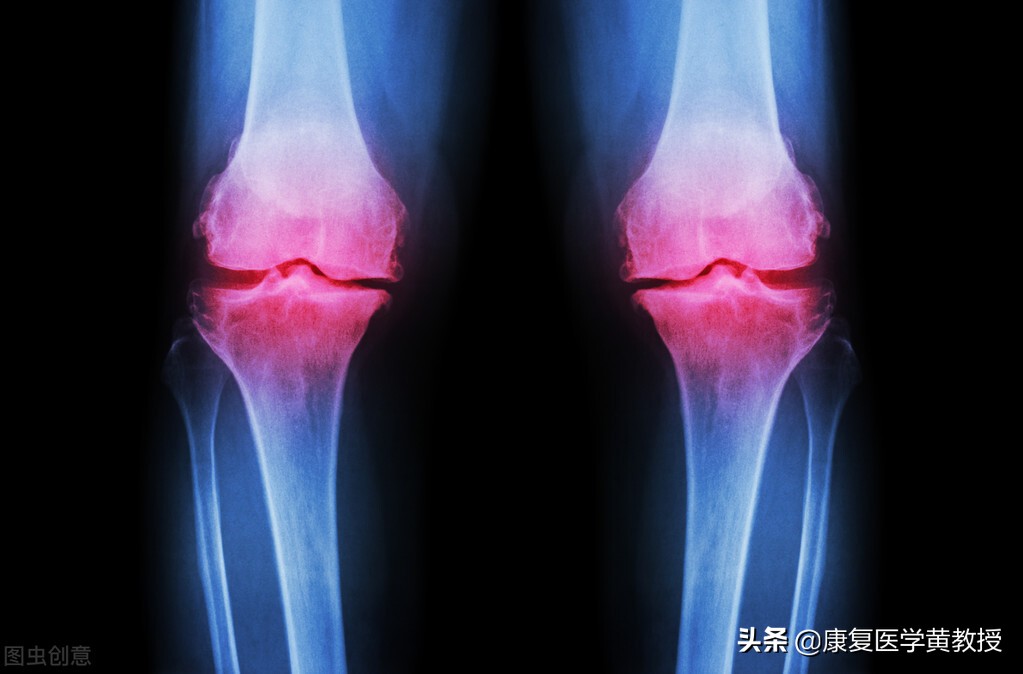

各位发现了吗?几乎所有发生骨质增生的部位,都与地心引力承重相关,颈椎-腰椎,髋关节,膝关节,踝关节及足跟,这些部位经过长时间的使用或过度使用(比如职业竞技选手),都会出现骨质增生现象,而骨刺本生的构造,就像我们的骨头是一模一样的,属于緻密型的结缔组织,其中也是蛋白质和钙离子等成分组成,因此我们应该将骨刺视为是人体的一部分,只是当我们出生的时候,这些结构并未出现,骨刺的出现,或许也是人类为了适应环境的挑战而衍生出来的防卫机制!

骨刺一旦出现即不可能消失,它最大的作用是为了让身体上的承重关节,进一步提升稳定度,比如膝关节,而骨刺增生所提示的另一个深层意义,代表身体机能的快速下降,因此我认为骨刺增生是人体最聪明的防卫机制,其实不是生病了,而是透过骨刺来提高我们能直立的本能.甚至保有行走的能力, 所以我们并不需要去按摩或贴膏药来想着消除骨刺,因为这是不可能的,如果透过这些方法就能消除骨刺,那麽我们的骨头不也就同时被消灭了?想想这些广告真是挺有趣的.

只是,骨刺增生有好的一面,必然也可能有弊端,比如膝关节开始骨质增生,同时代表的是半月板开始丧失缓冲减震的能力,只好利用骨头来分担压力,同时因为骨刺占据了原本不应该存在的空间,使得关节腔变小变窄,而影响膝关节的关节动力学表现,比如肌力下降,关节活动度下降,无法蹲起,生活品质下降,甚至加大腰椎与髋关节的压力,引发一系列的不正确的代偿模式,各位发现了吗?膝关节疼痛的患者,75%以上都伴随着腰痛或腰椎间盘膨出现象,这都是人体的连锁反应,无可避免.